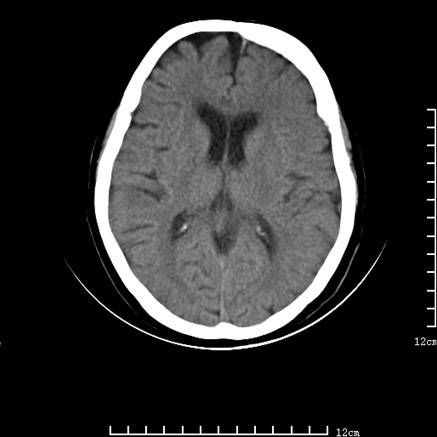

标题: V0514:女,72岁,偶有头晕,自诉记忆力减退,来诊。 [打印本页]

标题: V0514:女,72岁,偶有头晕,自诉记忆力减退,来诊。

是拉特可囊肿(rathke cyst)吗?

考虑垂体瘤可能性大

1、考虑垂体腺瘤。

2、脑萎缩ct表现。

垂体腺瘤可能性大!另:轻度脑萎缩!

考虑垂体腺瘤可能性大。脑萎缩。

考虑垂体腺瘤可能性大。脑萎缩。  建议mri 检查

垂体瘤,建议mri

垂体腺瘤